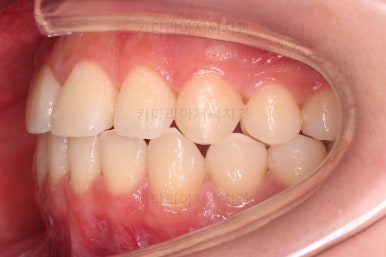

약간의 주걱턱 느낌에 약간의 돌출감, 전반적인 치열의 가지런한 느낌은 나쁘진 않았지만 약간의 불량한 교합상태였어요.

다른 부분은 크게 바꾸지 말고 약간의 교합 조절과 어금니 치료에 초점을 맞춰서 교정치료 계획을 잡았습니다.

장치를 부착했을 때 입이 나오는 느낌, 웃을 때 보이는 느낌은 참고해 주세요.

약간의 주걱턱, 돌출입은 고칠 의사가 없어서 그대로 유지하였고 주걱턱 패턴으로 인한 부정교합 부분을 개선했으며 무엇보다 중요한 것은 쓰러져서 많이 썩어있던 치아를 자칫 치료 못할 뻔 했는데 교정치료와 병행하여 훌륭하게 치료를 하여 살려 썼다는 점입니다.